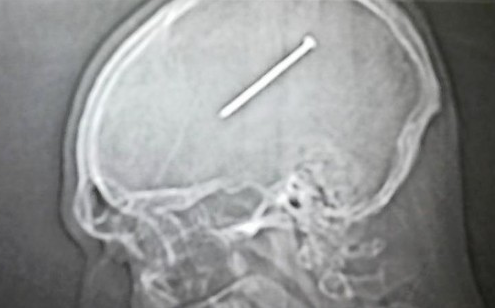

Kerroimme taannoin tapauksesta, jossa mies oli elänyt 25 vuoden ajan luoti päässään tietämättä siitä lainkaan. Luoti paljastui yllättäen röntgenkuvasta. Nyt toinenkin amerikkalainen mies on kokenut hieman samanlaisen yllätyksen, kun hänen päästään löytyi pitkä naula.

Dante Autullo oli ollut tekemässä remonttia autotallissaan, kun hän horjahti tikkailla ja naulapyssy iskeytyi hänen päähänsä. Mies huomasi iskusta aiheutuneen haavan, mutta ei kuitenkaan mennyt sen takia sairaalahoitoon, Chicago Tribune uutisoi. Hän ei kuitenkaan tiennyt, että naulapyssy oli samalla myös lauennut.

Kuva: Advocate Christ Medical Center

Tapauksen jälkeen mies palasi kokonaiseksi päiväksi töihin ajamaan trukkia ja vei myös lapsensa urheiluharjoituksiin. Vasta tämän jälkeen otettujen päiväunien jälkeen mies tunsi itsensä huonovointiseksi ja päätti mennä sairaalaan. Siellä hänen päästään löydettiin yli kymmensenttinen naula. Se saatiin lopulta poistettua leikkauksessa.